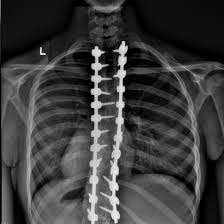

Scoliosis is often misunderstood — both by patients and sometimes even by healthcare providers. Many people think scoliosis is something you just “watch” or “wait out” until it causes pain. But the reality is far more complex.

Scoliosis is a structural condition involving spinal curves that don’t correct themselves overnight. A single chiropractic adjustment or pain relief session might help temporarily, but lasting improvement requires a consistent, personalized treatment plan.

Scoliosis often doesn’t cause pain until the curve has worsened significantly. By the time discomfort sets in, more invasive interventions might be necessary.

“Monitoring” scoliosis without intervention is a passive approach that can allow curves to worsen over time. Many cases can be managed effectively with non-surgical, conservative treatments if addressed early.

Our approach: We commit to transparency. We review your X-rays and progress with you, explain what’s happening, and work together on a realistic, actionable plan.